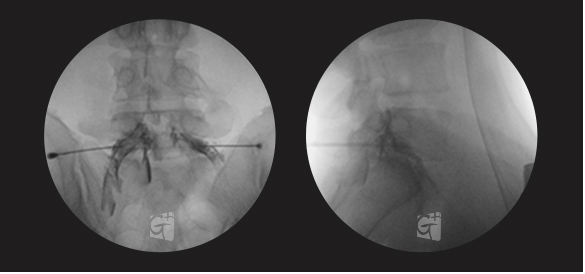

요추 신경성형술

꼬리뼈 구멍으로 카테타 삽입

척추관 안쪽으로 진입 약물 주입

원인부위 염증 제거 및 유착 박리

유착박리로 추간공 확보, 신경 압박 감소

척추관에서 약물이 잘 퍼져나오는 모습

허리 신경 전체를 효과적으로 치료